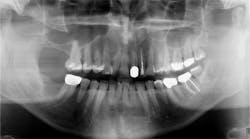

When a radiograph is taken, the dental professional may see what appears to be the outline of the root socket where an extraction has occurred, usually many years prior to any complaints (figures 1 and 2). This is a residual socket or residual root socket. The outline of the tooth’s root cavity is faintly visible, and when examined surgically, it may be hollow or filled with dense fibrous scar tissue, granulation tissue, or very immature bone.

Figure 2: Residual sockets in the same left mandible. Courtesy of Dr. Jerry E. Bouquot.